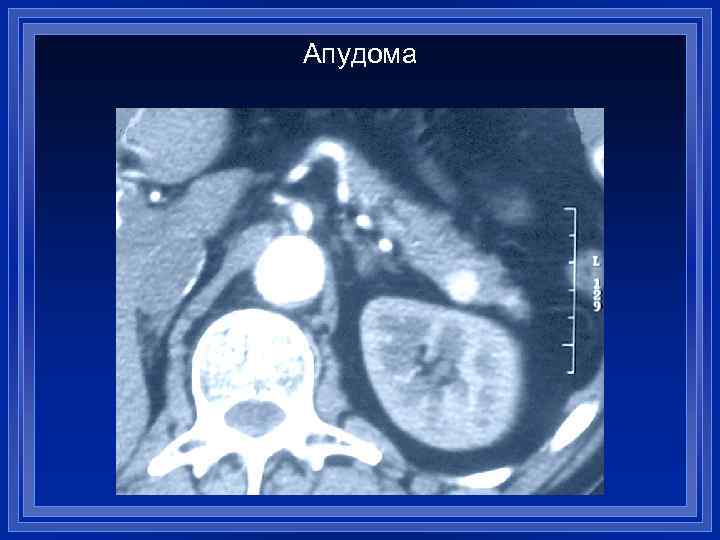

Апудома